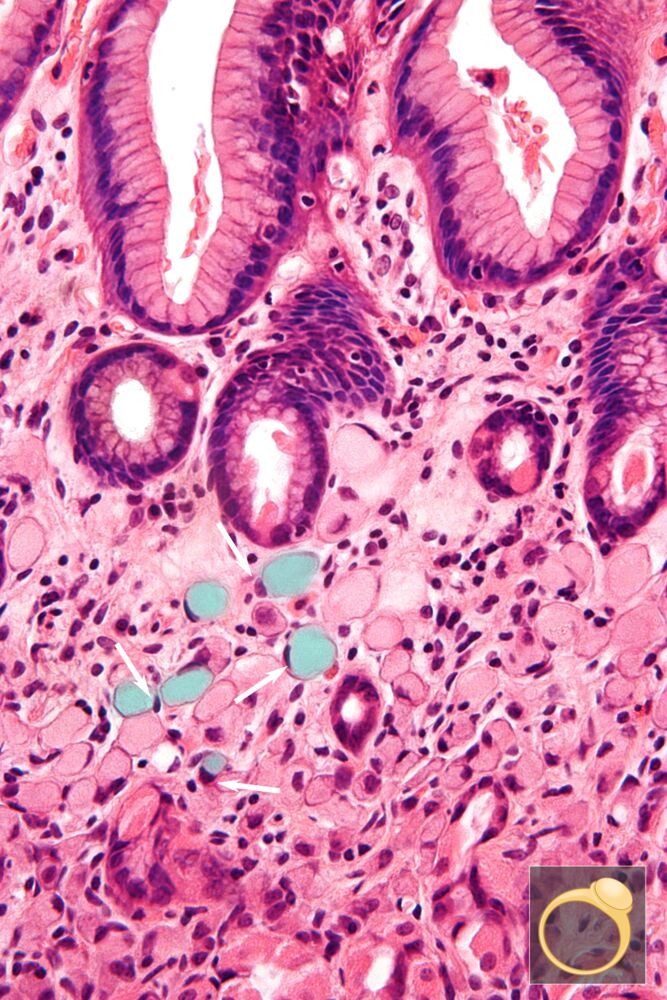

Gastric Signet Ring Cell Carcinoma

Multiple cells with peripheral nuclei (examples indicated by white arrows) and engorged cytoplasm (examples indicated by green overlay) are visible.

These morphological features are characteristic of gastric signet ring cell carcinoma.